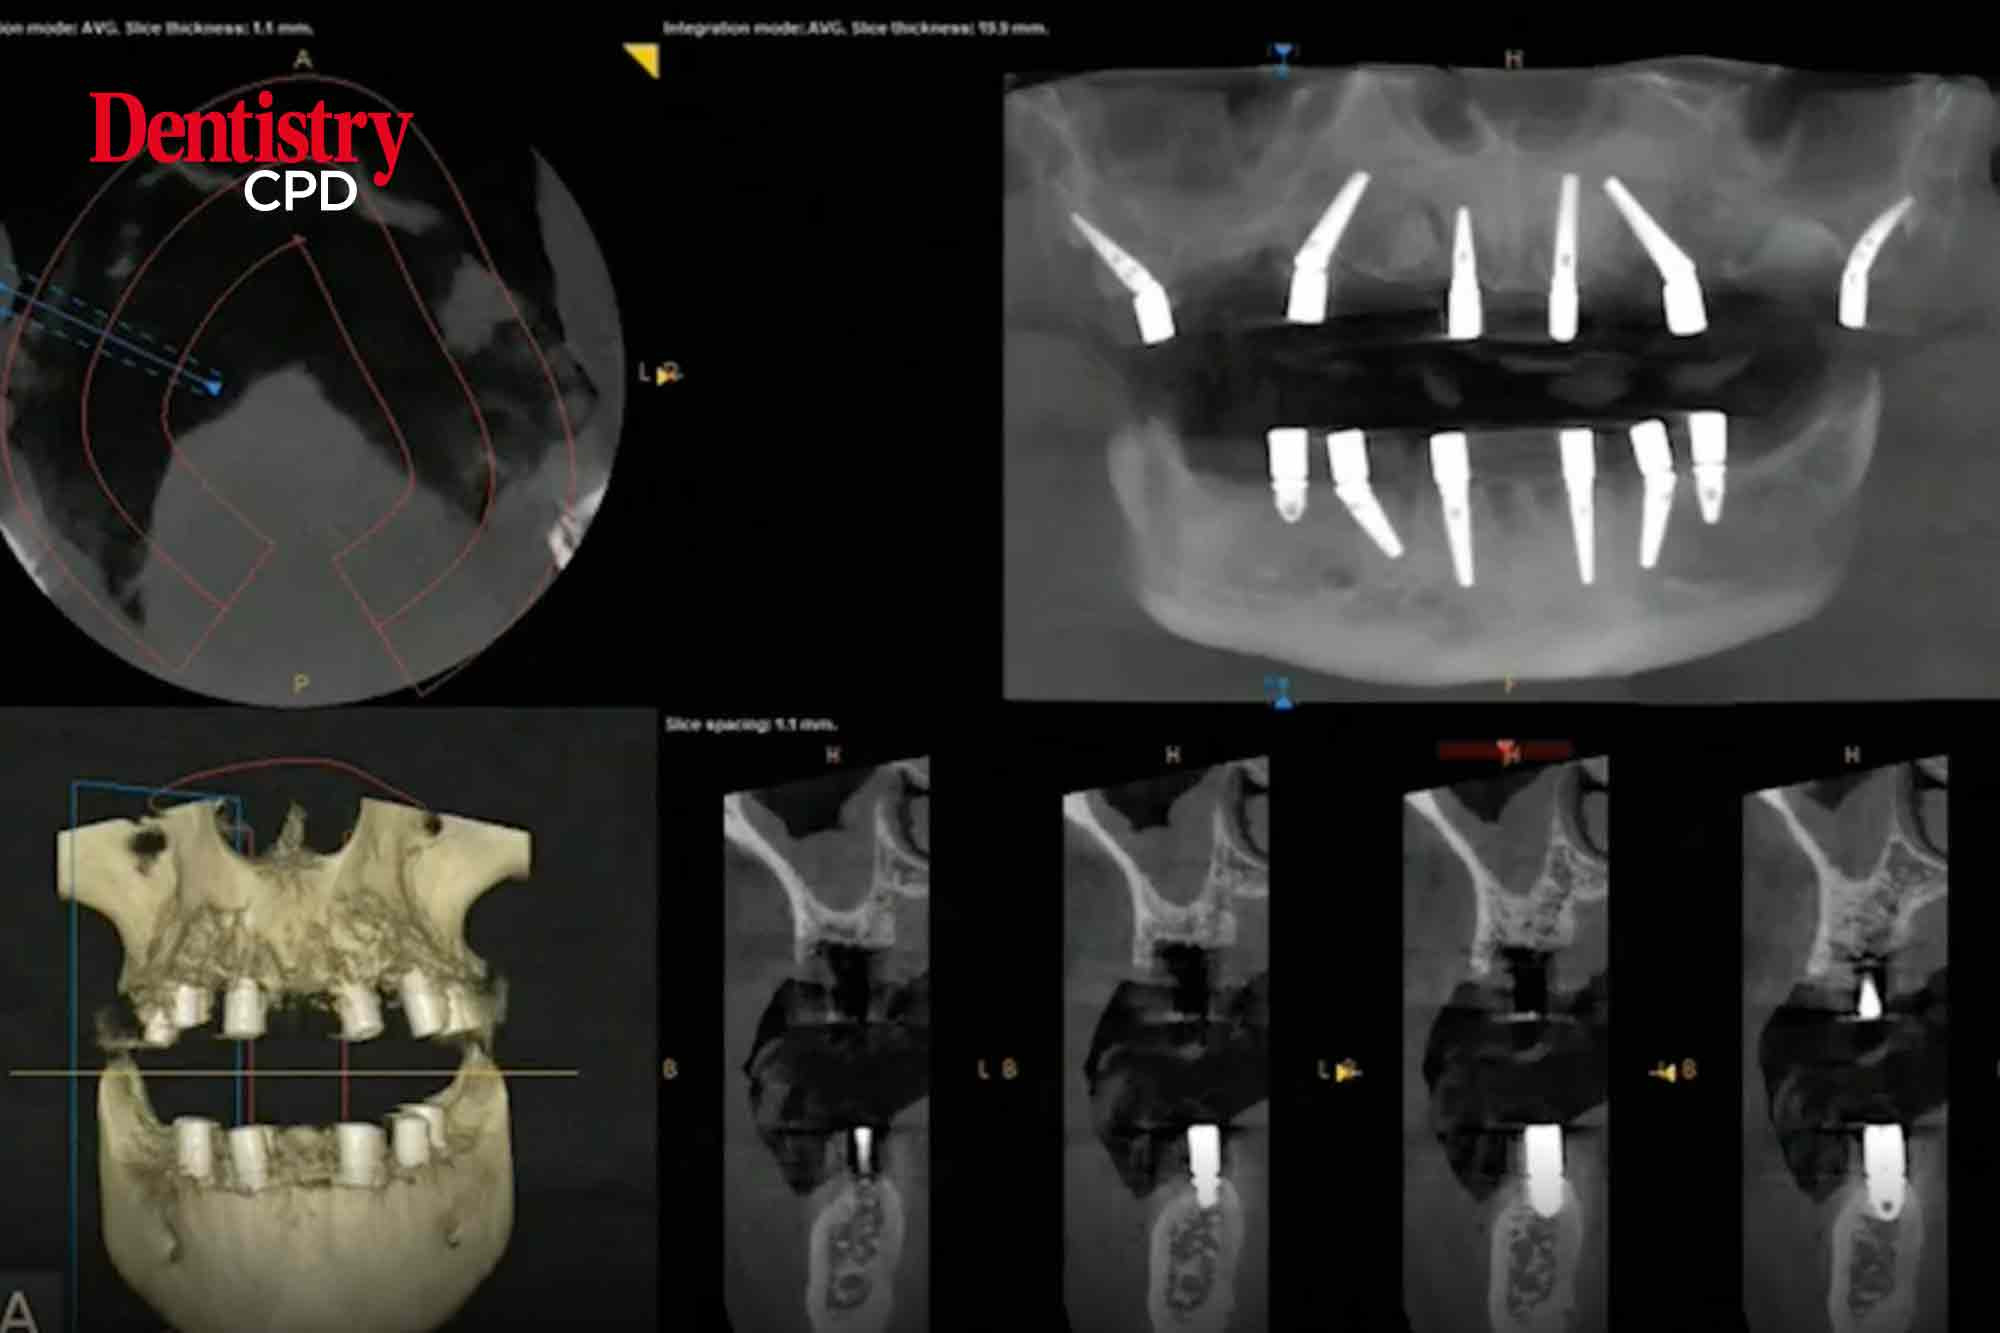

This webinar features a pre-recorded full arch implant rehabilitation (FAIR) surgery, and associated digital workflow, showcasing the use of Imetric photogrammetry.